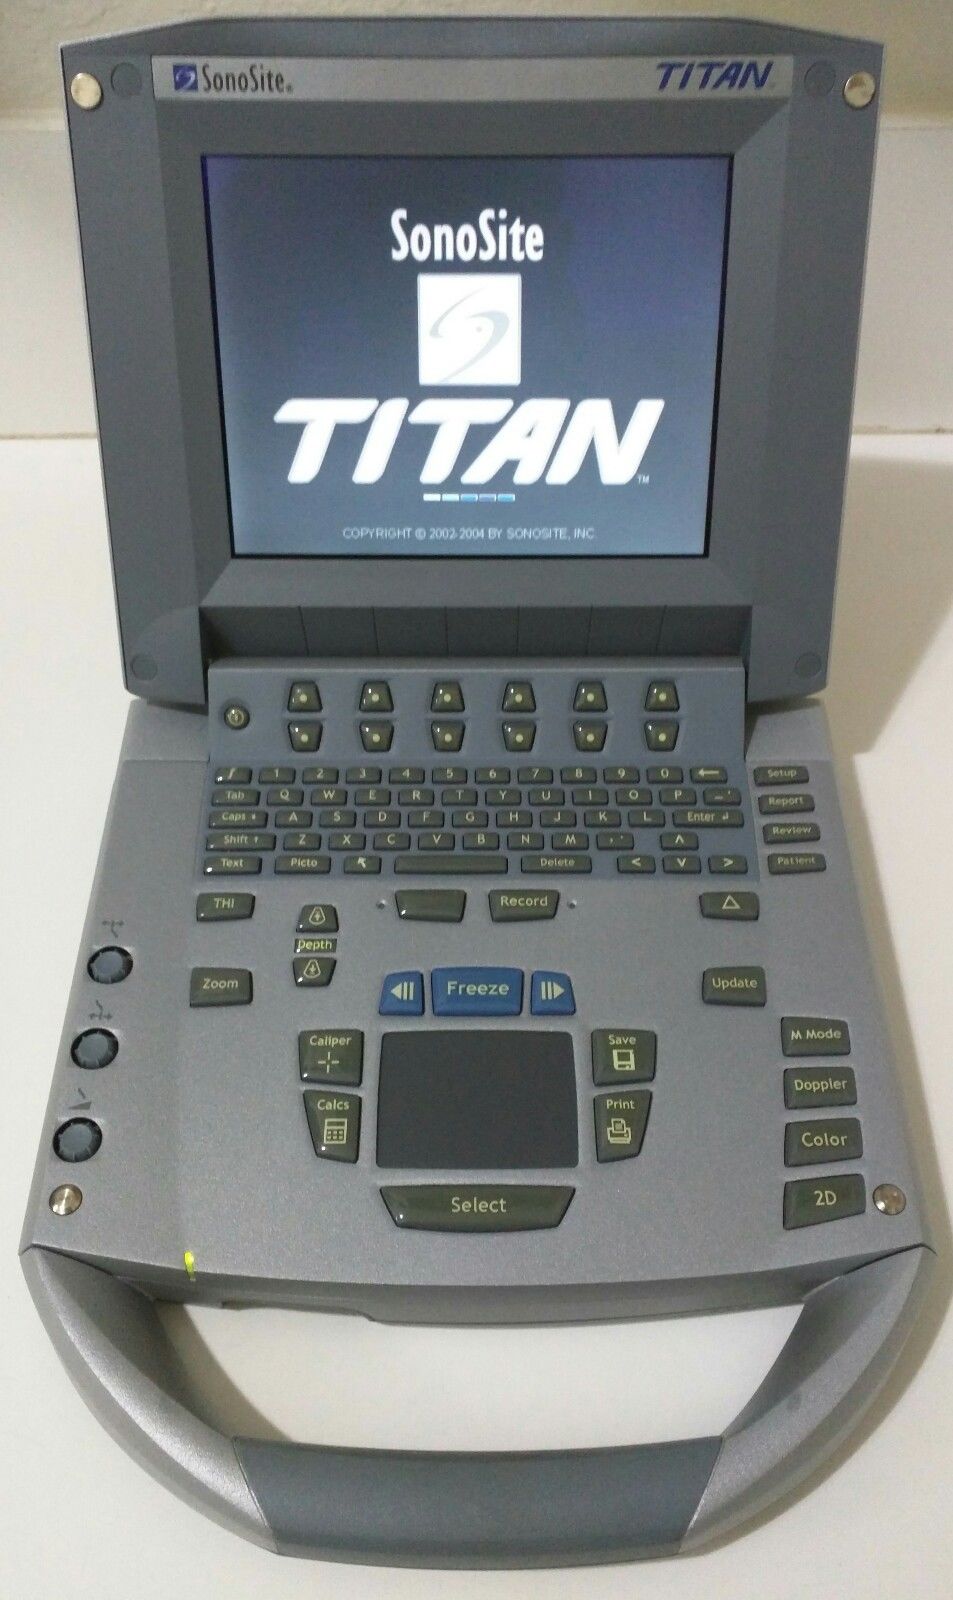

SONOSITE TITAN OB/GYN Ultrasound: Advanced Imaging Solutions

Seller Notes:â"This unit was fully refurbished, right now is Like a New"â

Model: Titan

Brand: SonoSite

The SONOSITE TITAN OB/GYN ultrasound offers state-of-the-art imaging technology. This device uses advanced algorithms to provide clear, high-resolution images. It includes two probes: a 1-C60 convex and a 1-ICT transvaginal probe, ensuring versatility in different obstetric and gynecological applications. Because of its compact design, the SONOSITE TITAN is perfect for both hospital and remote settings, making it an ideal choice for healthcare providers.

User-Friendly Interface

Designed with usability in mind, the SONOSITE TITAN features an intuitive interface that simplifies operation. Clinicians can easily switch between modes and access images quickly. This efficiency is critical during patient exams, allowing for quicker diagnoses. Additionally, its lightweight design enhances portability without sacrificing performance, allowing healthcare professionals to take it where it's needed most.

Durability and Reliability

The SONOSITE TITAN is built for durability, capable of withstanding the demands of a busy clinical environment. Its robust construction ensures reliability, meaning that healthcare providers can trust it during high-pressure situations. Furthermore, regular updates to its software keep it at the forefront of medical imaging technology, ensuring continuous improvement and long-term satisfaction for all users.